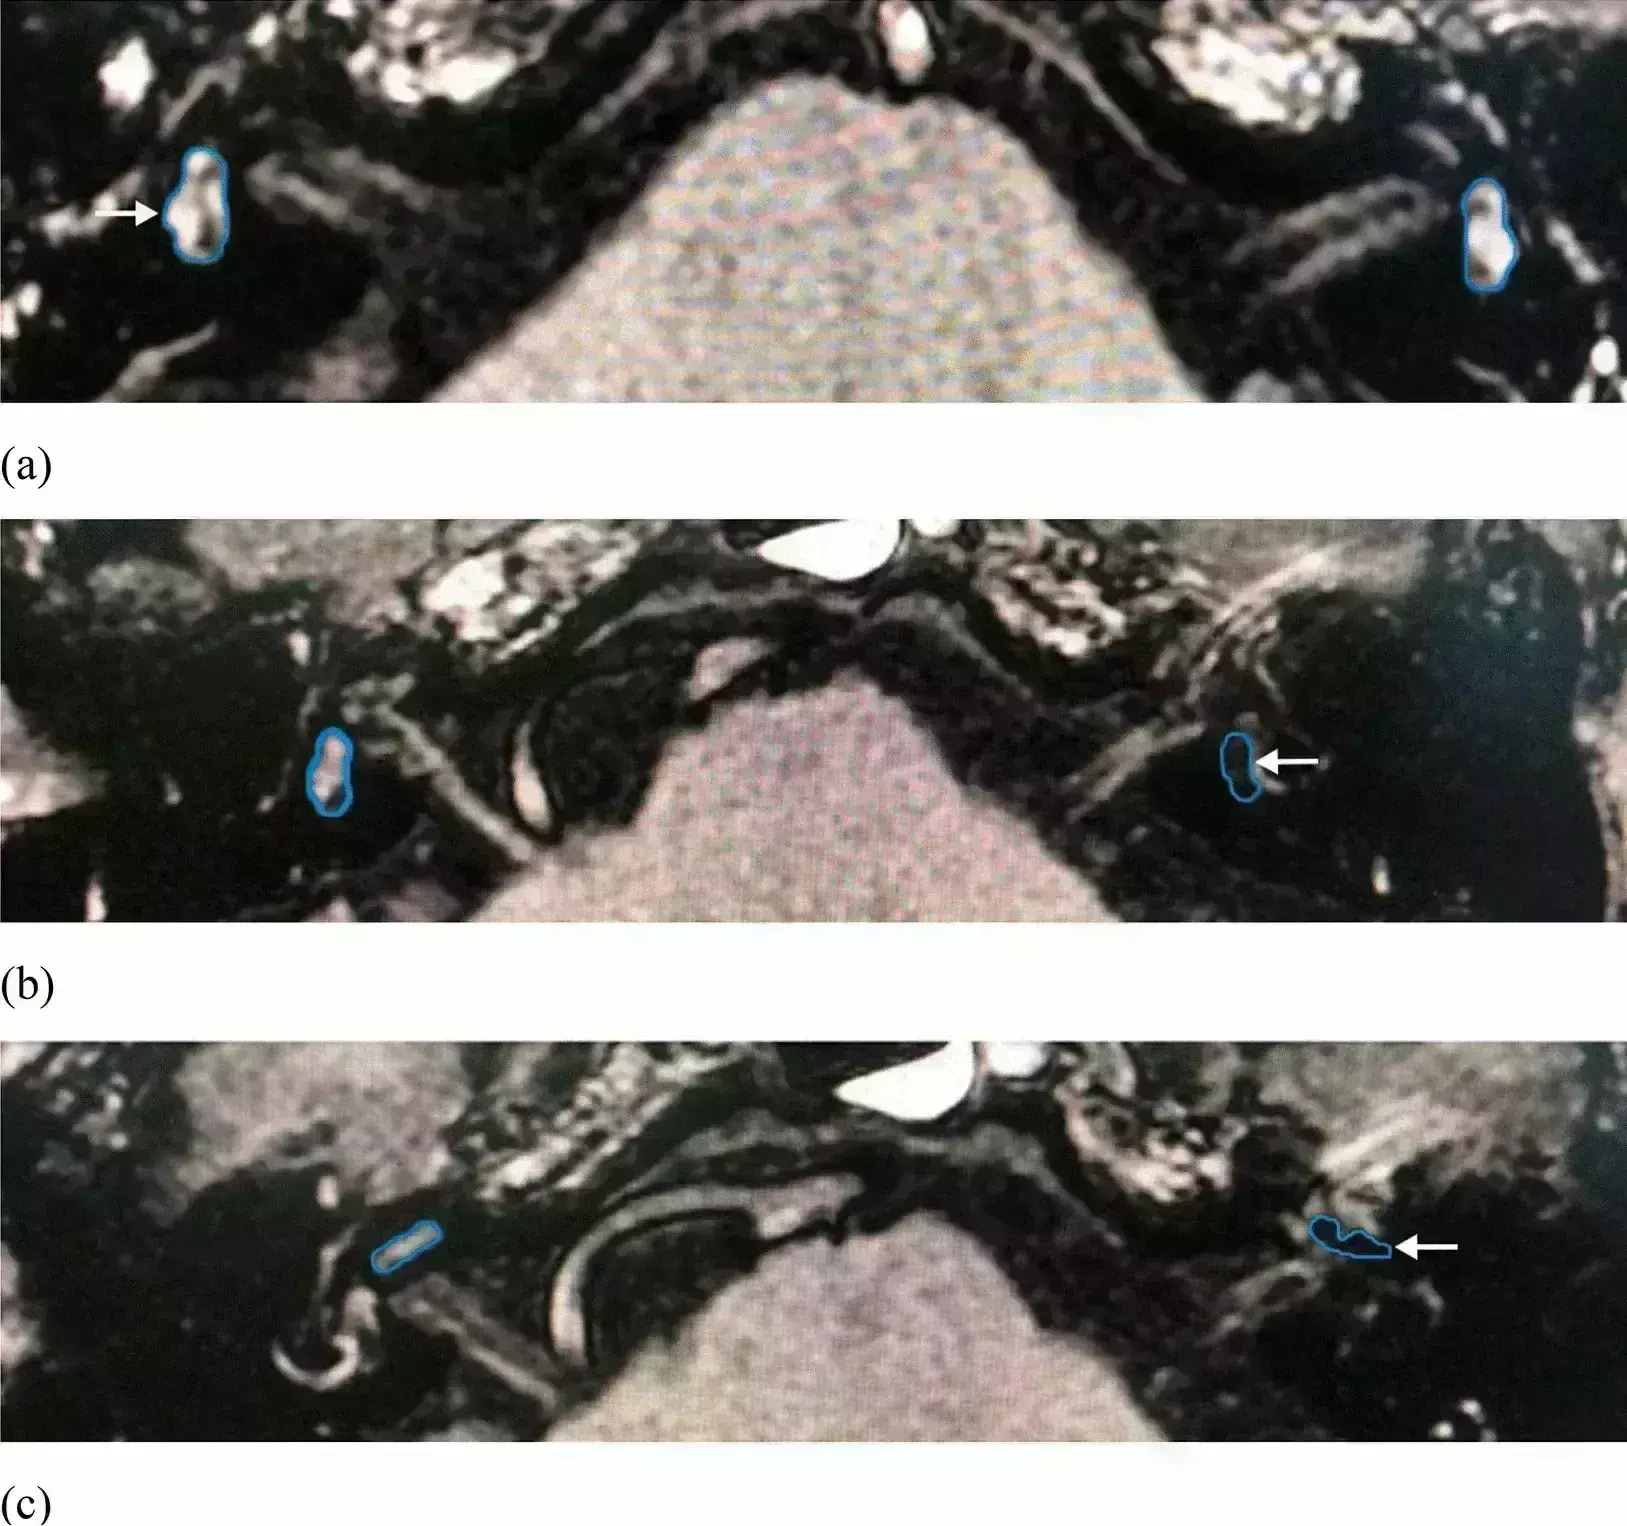

USA: A new retrospective analysis has unveiled a striking radiological signature in Meniere’s Disease (MD) with comorbid migraine patients, revealing that bilateral Endolymphatic Hydrops (EH) is significantly more prevalent than in isolated MD cases.The analysis was published in the journal Medical Sciences in January 2026.Migraines frequently coexist with MD, often complicating the interpretation of clinical diagnoses and inner ear imaging. While EH has been studied in both conditions independently, comparative imaging data for MD patients specifically with and without migraine remain scarce. To address this gap, Yoshiyuki Sasano of the University of Miami Miller School of Medicine and colleagues aimed to evaluate the EH in MD patients with and without migraine.For this purpose, the researchers conducted a retrospective analysis on 78 patients with definite MD, comparing 56 isolated cases against 22 with comorbid migraine using 3.0 Tesla Magnetic Resonance Imaging (MRI). Utilizing the HYbriD of the reversed image of the positive endolymph signal and native image of the positive perilymph signal (HYDROPS) technique, investigators graded EH severity in the cochlea and vestibule four hours post-contrast, excluding subjects with bilateral MD, claustrophobia, or contrast allergies.Key Findings of Analysis Include:Bilateral Hydrops Prevalence: The analysis unveiled that bilateral EH was significantly more frequent across all inner ear regions in the MD with migraine group compared to isolated MD cases.Symmetrical Fluid Signature: Investigators found that MD patients with comorbid migraine exhibit a unique symmetry in EH distribution, showing no significant interaural differences in the inner ear, vestibule, or cochlea.Healthy Cochlear Involvement: A significant EH occurred at a significantly higher frequency in the clinically healthy cochlea of the comorbid migraine group (40.9%) than in the isolated MD group (3.6%).Earlier Clinical Presentation: The MD patients with comorbid migraine present at a significantly younger mean age of onset (40.1 years) and age of examination (42.8 years) compared to those without migraine.Diagnostic Imaging Indicator: Authors conclude that detecting bilateral hydrops via the HYDROPS technique in suspected MD cases should prompt an immediate evaluation for comorbid migraine.The results suggest that patients with MD and comorbid migraine exhibit a distinct radiological signature of bilateral and symmetrical EH, often involving the clinically healthy ear. The author emphasizes that clinicians should consider evaluating for comorbid migraine when detecting bilateral endolymphatic hydrops on imaging in suspected Meniere’s disease cases, rather than attributing the findings solely to bilateral disease or asymptomatic fluid accumulation.They acknowledged that the study’s retrospective nature and limited sample size in the comorbid group may constrain the evaluation of specific vertigo triggers and the identification of subtle intergroup differences, which future larger prospective cohort research could further clarify.ReferenceSasano, Y., Mochizuki, F., Ito, Y., Williams, E., Koizuka, I., Hoffer, M.E., & Komori, M. (2026). Characterizing Differences in Endolymphatic Hydrops Signatures Among Meniere’s Disease Patients with and Without Migraine. Medical Sciences, 14(1), 29.